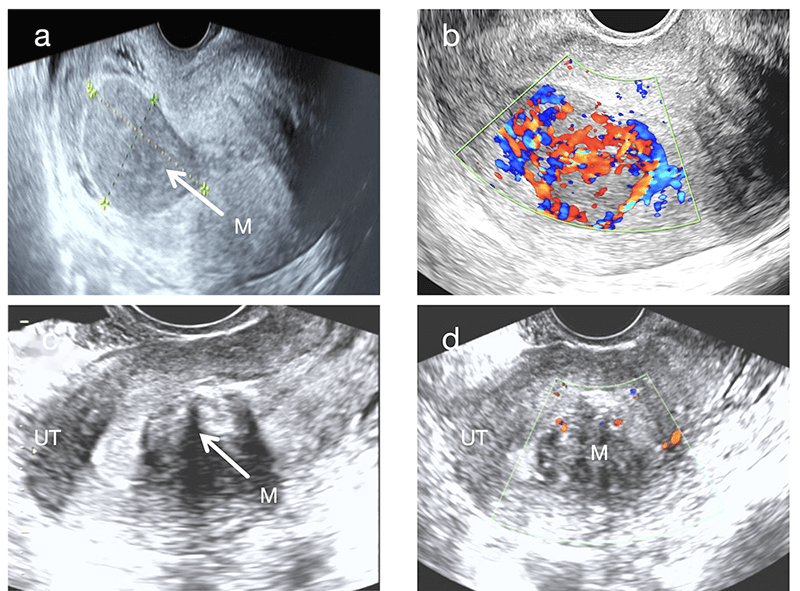

In terms of internal echogenicity, UIMT typically presents as hypoechoic, although hyperechoic appearances can also occur. The latter may be associated with increased tumor cell cellularity and pronounced inflammatory cell infiltration (Fig. 1a). Moreover, most UIMT lesions exhibit heterogeneous internal echoes, likely resulting from the irregular interlacing of collagen fibers within the tumor stroma [9].

Fig. 1.

Ultrasonographic and Pathological Images of Case 2. (a)

Sagittal 2D ultrasound image showing a hyperechoic mass in the posterior uterine

wall with a “blurred halo sign”. (b) Color Doppler ultrasound demonstrating

abundant intralesional blood flow signals (Adler grade 3) with a “colorful

mosaic sign”. (c) T2-weighted MRI revealing a slightly hyperintense mass. (a,b,c)

White arrows indicate the tumor masses. (d) HE staining (100

In this study, all 6 cases of UIMT presented as solid masses, in agreement with the findings of Bai et al. (2024) [6]. Therefore, the presence of solid components may be considered a characteristic sonographic feature of UIMT. Zhao et al. (2022) [10] described a case of UIMT containing cystic components, possibly arising from inflammatory infiltration, intratumoral hemorrhage, or cystic necrosis.

A key observation in this study was the “blurred halo sign”, identified as a typical ultrasonographic feature of UIMT. This sign is characterized by scattered strip-like or patchy hyperechoic areas within a hypoechoic background (Fig. 1a, Fig. 2a). It is clearly distinguishable from the “whorled pattern” typically observed in conventional leiomyomas (Fig. 2c). In leiomyomas, heterogeneous hypoechoic or isoechoic areas create whorled textures due to interwoven smooth muscle cells and connective tissue fibers. In contrast, UIMT lesions display more homogeneous, dense internal echoes. Its signal on magnetic resonance imaging (MRI) also appears relatively homogeneous (Fig. 1c), whereas leiomyomas generally show lower and more disorganized echogenicity (Fig. 2a,c). However, overlap in imaging features may occur when leiomyomas undergo degenerative changes, such as mixed echogenicity or cystic transformation [11]. In such instances, the diagnostic utility of the “blurred halo sign” when combined with abundant blood flow signals becomes even more prominent.

According to the latest WHO classification, UIMT includes three histological subtypes: (1) Loosely arranged myofibroblasts with mucus, rich vessels, and inflammatory infiltration; (2) Densely packed spindle cells with mucus or collagen regions; and (3) Scar-like hyperplasia with scattered inflammatory cells. All 6 cases in this study presented features of the myxoid and dense spindle-cell types (Fig. 1d), with mild cellular atypia and abundant cytoplasm—features that can lead to misdiagnosis as uterine leiomyoma or spindle cell sarcoma [25, 26]. Thus, accurate diagnosis requires an integrated assessment combining histopathology and immunohistochemistry, with ALK expression and rearrangement serving as key criteria.